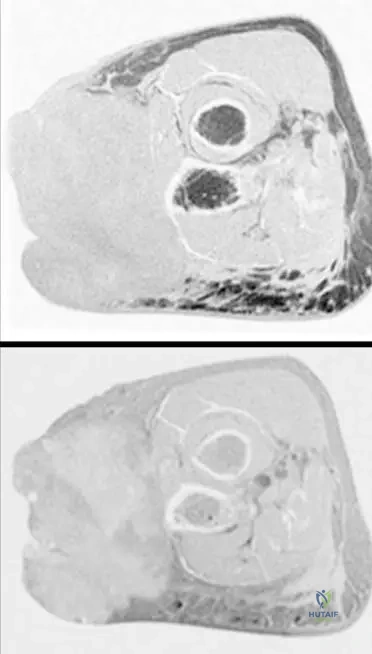

Question 13

A 63-year-old male presents with a deep-seated mass in his thigh. An MRI is performed to characterize the lesion. The axial T1-weighted image is shown.

View Answer & Explanation

Correct Answer: A

Rationale: The clinical context for Fig. 9.19 states: "Axial T1(a) and axial T2-weighted MRI with fat saturation (b) showing typical MRI features of a soft tissue sarcoma with intermediate signal intensity on T1 (isointense with muscle)." Main Distractor: B) Markedly high signal intensity, brighter than fat. This is incorrect; T1 signal for STS is typically intermediate, isointense with muscle, not markedly high like fat.

Question 14

A 63-year-old male presents with a deep-seated mass in his thigh. An MRI is performed to characterize the lesion. The axial T2-weighted MRI with fat saturation is shown.

Rationale: The clinical context for Fig. 9.19 states: "Axial T1(a) and axial T2-weighted MRI with fat saturation (b) showing typical MRI features of a soft tissue sarcoma with intermediate signal intensity on T1 (isointense with muscle) and markedly heterogeneous predominantly high signal intensity on T2." Main Distractor: B) Homogeneous low signal intensity. This is incorrect; sarcomas typically show high signal on T2, and often with heterogeneity, not homogeneous low signal.

Question 15

A 63-year-old male presents with a deep-seated mass in his thigh. An MRI is performed to characterize the lesion and its anatomical origin.

Rationale: The clinical context for Fig. 9.19 states: "Note that the tumor originates within the deep muscular compartment of the thigh." Main Distractor: B) Subcutaneous compartment. While some sarcomas are subcutaneous, the text specifically states this particular tumor (Fig 9.19) originates in the "deep muscular compartment."